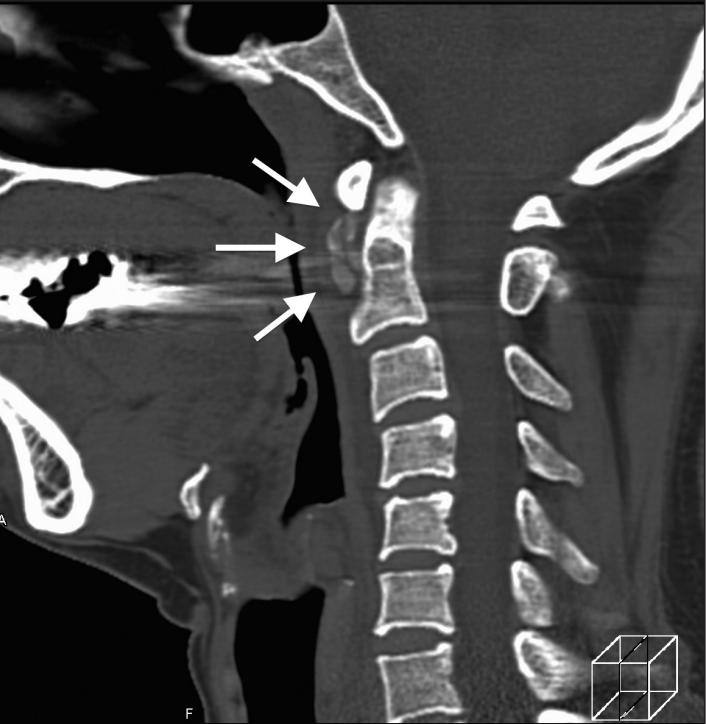

明确诊断主要通过影像学方法,颈椎CT是关键。 颈长肌钙化性肌腱炎特异性的影像表现是C1-4椎体前缘软组织肿胀和积液与C1椎体前弓下方不规则钙化沉着共存。

图:C1椎体前弓下方不规则钙化沉着

CT的高分辨率能够明确肌腱内的钙化,能够明确是钙化而不是其他骨骼来源的高密度影。 钙化一般位于寰椎前弓的下方和枢椎齿状突的前方,少部分可位于下颈椎前侧 。CT有助于明确椎体前积液的存在和排除其他病理表现,如骨折或脓肿。MRI对诊断不是必须,但有时可帮助确定软组织异常,排除咽后脓肿,脊椎炎或肿瘤。 MRI检查T2加权在椎前可见局限性的裂隙样区域,大多位于C1-4水平,呈高信号改变,这反应是由于炎症引起的积液 。T2加权、脂肪抑制序列和T1加权对鉴别积液和脂肪组织、含脂肪的骨髓以及咽后感染、脊椎炎有重要作用。MRI检查在钙化检查方面存在不足,T2加权呈低信号。

40岁男性,低热伴急性颈痛、张口困难1天,颈椎CT提示椎前钙化(箭头),经洛索洛芬60mg,每日三次,连续五天治疗,3天后症状改善,3月复查CT钙化消失。(PMID: 25918175)